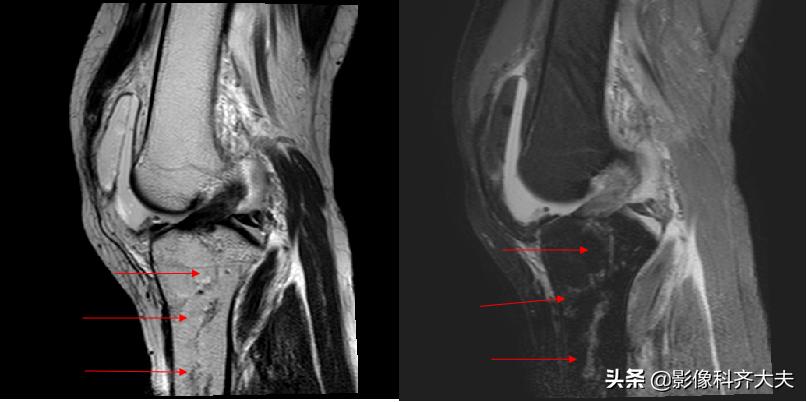

骨挫伤(bone bruise):外力作用引起的骨小梁断裂和骨髓水肿、出血,T1WI低信号,T2WI高信号,压脂序列显示清晰。平片和CT 上常无异常发现。

右胫骨骨挫伤-MRI清晰显示病灶位置

胫腓骨骨挫伤

胫腓骨对应性骨挫伤